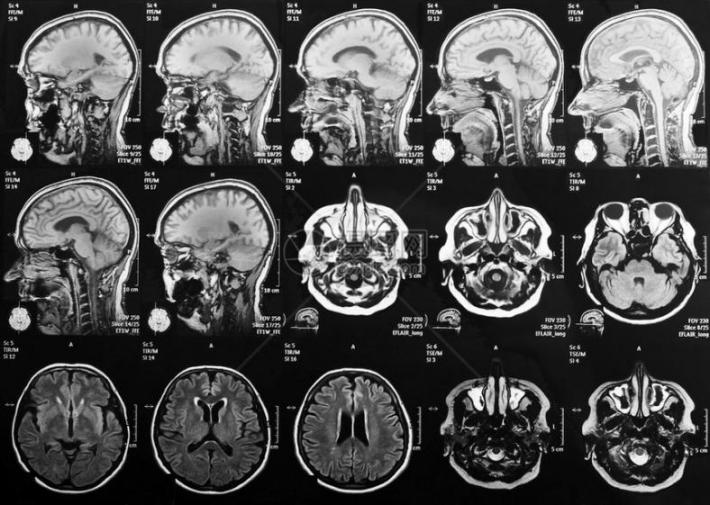

我们每天都在思考,但思考时大脑里发生了什么?利用磁共振成像设备(MRI),科学家们就如同操作一台超级‘大脑摄像机’,使得我们能‘看见’大脑的活动。

磁共振成像(MRI)就像是一种用强磁场给大脑照片的技术。人体内富含氢原子,这些氢原子在强磁场里会排好队,像小磁铁一样。这时,机器会发射出一种特殊的信号,短暂地“推”或“打扰”一下这些小磁针,让它们的队形暂时乱了。等这个“信号”停止后,被推乱的小磁针又会努力转回原来的方向。就在它们转回去的过程中,自己也会发出微弱的信号。机器捕捉到这些返回的信号,经过处理,就变成了我们看到的大脑清晰图像。

人脑在执行特定任务(如看图片、做数学题、回忆事情)时,与该任务相关的脑区可能会被激活。 科学家们借助fMRI可获得人体大脑在这些任务状态下的图像数据,通过对比不同任务下的大脑激活图,就能知道哪些脑区参与了特定类型的思考或感知。比如,观看人脸时,与面孔识别相关的‘梭状回面孔区’可能会被激活。

通过探测不同任务状态下大脑的血氧变化,磁共振技术得以标识忙碌的脑区。这为研究大脑工作机制,理解大脑的各种功能提供了强大工具。